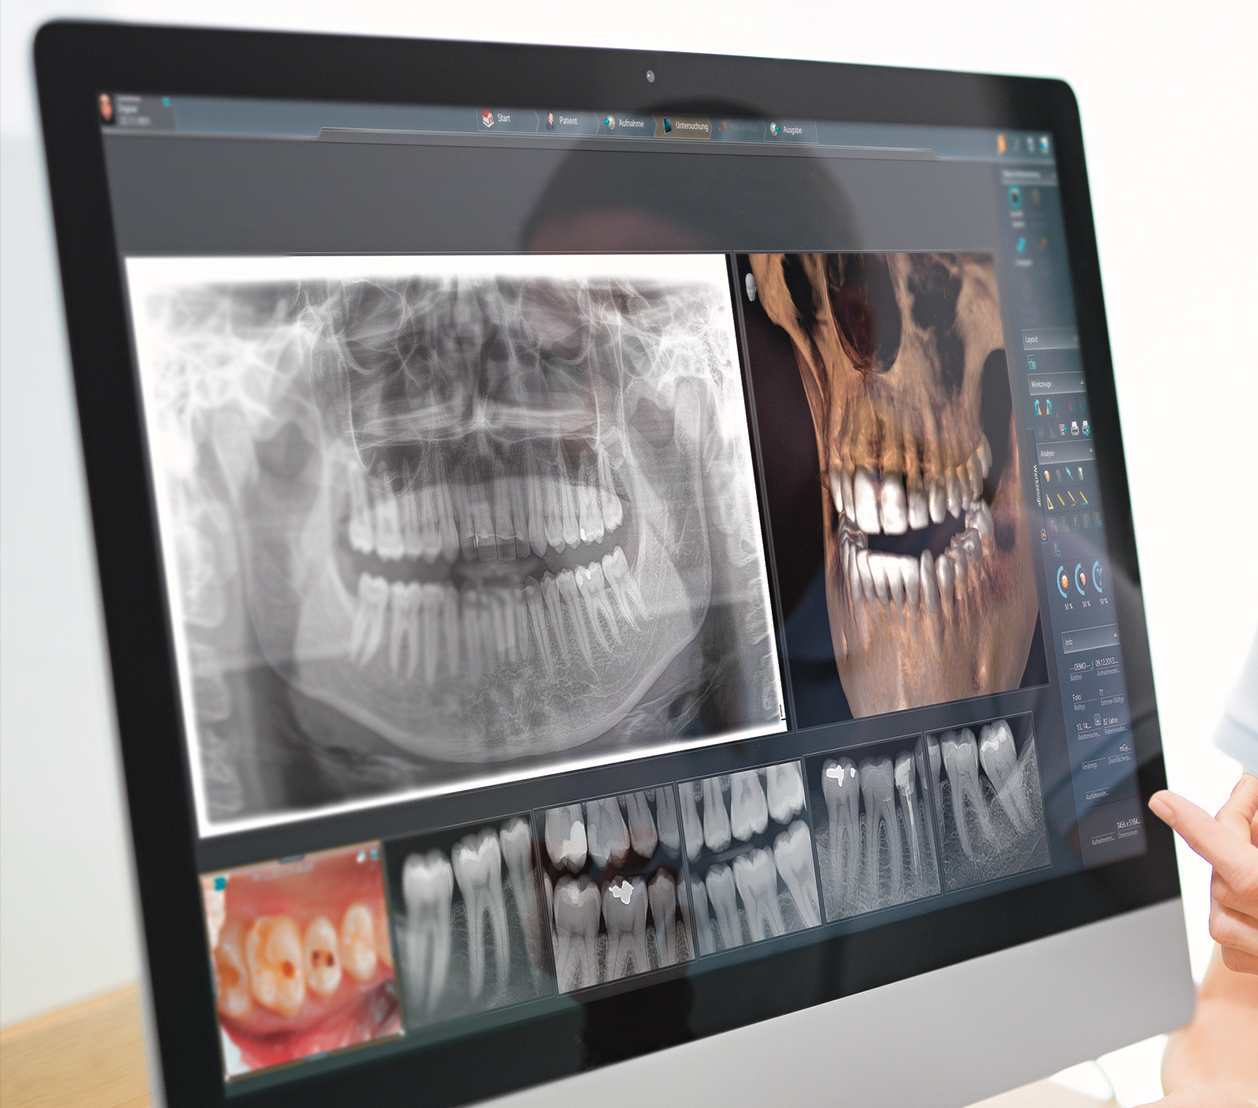

Die digitale Volumentomographie (DVT) ist ein fortschrittliches bildgebendes und strahlungsarmes radiologisches Verfahren, das speziell für die präzise Darstellung der Kiefer- und Zahnstruktur entwickelt wurde und hochauflösende Röntgenbilder und eine exakte 3D-Ansicht des Schädels erzeugt. Im Gegensatz zur herkömmlichen zweidimensionalen Röntgentechnik ermöglicht das strahlungsarme DVT-Röntgenverfahren eine dreidimensionale Visualisierung von Zähnen und Kiefern, was eine detaillierte Bildgebung der anatomischen Strukturen sowie der genauen Lagebeziehungen erlaubt. Das vorhandene Knochenvolumen, die Nasennebenhöhlen, kleinste Weichteilstrukturen sowie die genaue Position der Nervenbahnen werden dabei ohne Vergrößerung oder Verzerrung dreidimensional dargestellt.

Dies bildet zum einen die Grundlage für eine umfassende und präzise 3D-Röntgendiagnostik und ermöglicht zum anderen die optimale Planung verschiedener Behandlungen und kieferchirurgischer Eingriffe, wie sie in der Zahnarztpraxis Dr. Zieger in Bonn durchgeführt werden.

Ein entscheidender Vorteil der digitalen Volumen­tomographie (DVT) ist zudem die

enorme Reduzierung der Strahlenbelastung im Vergleich zur konventionellen Röntgentechnologie eines Standard-CTs bei gleichzeitigem Gewinn maximaler Informationen für eine präzise Röntgendiagnose. Aus diesen Gründen kommt die digitale Volumen­tomographie (DVT) in vielen Bereichen der Zahnmedizin zum Einsatz:

Die digitale Volumentomographie (DVT) stellt derzeit die fortschrittlichste am Markt erhältliche 3D-Röntgen-Technologie dar und ermöglicht es uns, Ihnen in unserer Zahnarztpraxis in Bonn modernste 3D-Implantatplanung mit digitaler 3D-Röntgentechnik auf höchstem Niveau anzubieten.